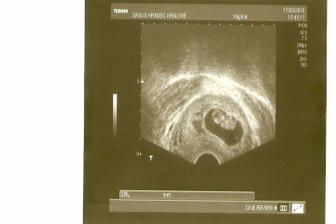

Že by ... ???

krásná čárečka gratuluju a přeju krásné těhulkování